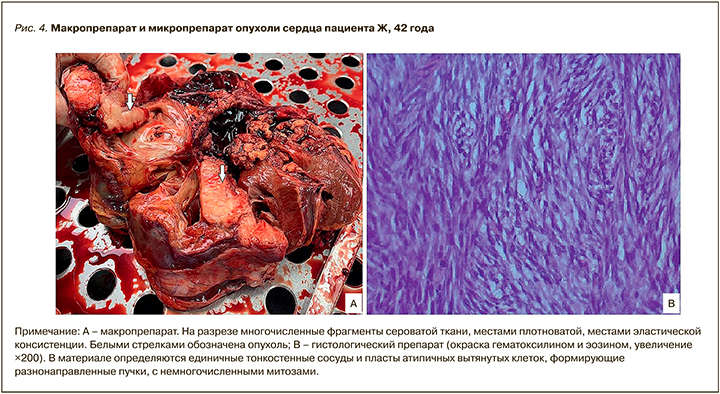

В условиях искусственного кровообращения 28.07.2021 пациенту было удалено образование правого предсердия и правого желудочка размером 10,7×9,5×8,2 см.

Заключение иммуногистологического исследования препаратов опухоли: недифференцированная плеоморфная саркома (рис. 4).